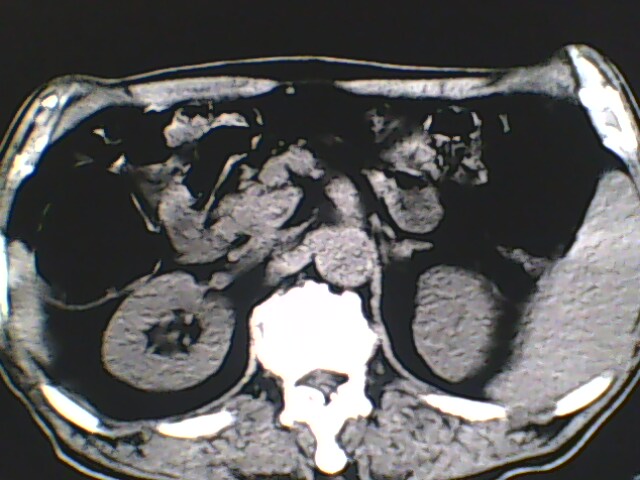

男,56岁,高血压,临床怀疑肾上腺问题,肝脏怎么那么高啊?能描述一下么?

右侧膈膨升,间位结肠,胸腰椎退行性骨关节病,右侧肾上腺可疑增生(图像颗粒太粗,窗太窄,不好看)。

支持 右侧膈膨升,间位结肠;胸腰椎退行性骨关节病;双侧肾上腺可疑增生。